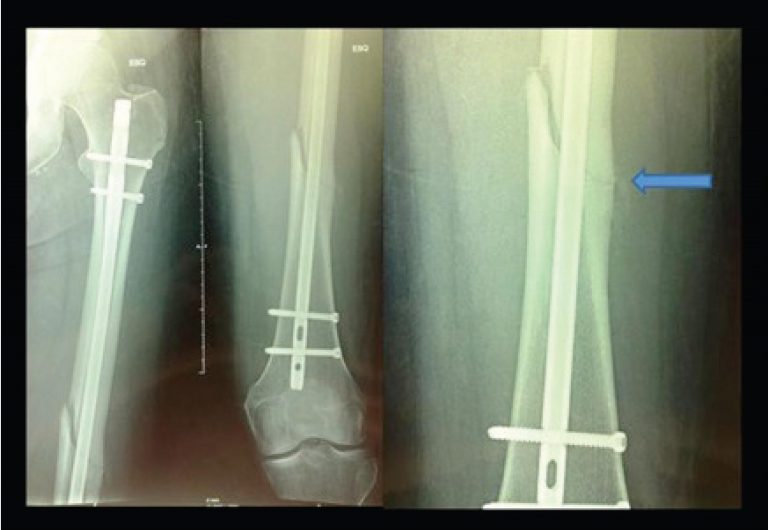

Fraturas diafisárias do fêmur por baixa energia nos pacientes idosos com uso prolongado de alendronato

Fraturas no fêmur proximal ocorrem em mulheres e homens idosos devido a trauma de baixa energia em ossos osteoporóticos. Recomenda-se o tratamento da osteoporose, especialmente com bifosfonatos, para tais fraturas sejam evitadas().

O alendronato foi o primeiro fármaco aprovado pelo Food and Drug Administration (FDA), em 1995, para tratar osteoporose(). Essa droga atua no metabolismo ósseo, ao inibir os osteoclastos, induzir sua apoptose(), elevar a densidade mineral óssea e reduzir a incidência de fraturas osteoporóticas().